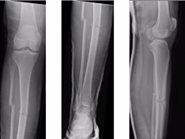

Olika metoder vid denna femurfraktur

Vad ser du, vad ska vi i regel välja?

A

• Lång platta för direkt läkning (kompressions-osteosyntes)

• Märgspik – indirekt läkning

o Väldigt bra. Tillåter belastning direkt (bra)

o Om märghålan är för smal så kör vi platta (annars alltid spik!)

Märgspik eller platta?

• Två bra bitar. Vi kan sätta ihop med platta och skruv men med märgspik kan vi belasta direkt.

• Om märghålan är för smal så kör vi platta (annars alltid spik!)

Q

23-årig kvinna påkörd av bil som cyklist. Vad göra?

Märghålan inte så stor så man mäter med DT och märghålan mäts till 6 mm (för litet (8-9 mm som minst)) därför platta om vi opererar men, vad kan vi göra också?

Tibiafrakturen ligger fint (odislocerad) så man kan gipsa i tre månader